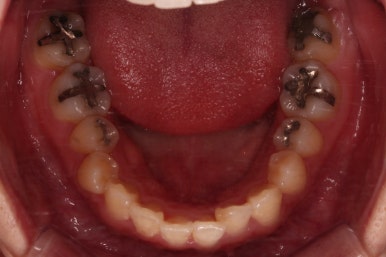

아랫니는 발치 없이 가지런하게 해주고요.

윗니는 가지런하게 한 뒤 발치공간을 서서히 닫아줍니다.

유치는 크기가 작았기 때문에 생각보다 빨리 공간이 닫히고 있고요.

반대쪽 작은 어금니 부분은 공간이 아직 많이 남은 편이죠.

매복치아 발치 부위의 앞니도 이미 뿌리가 약간 손상된 상태였기 때문에 교정 중에도 경과 관찰을 잘 해줘야 합니다.

미니스크류를 적절히 사용해서 부정교합도 맞추고 입매도 약간 들어가게 혹은 너무 들어가지 않게 조절해 주고요.

치열의 경사 등등도 조절해 줍니다.